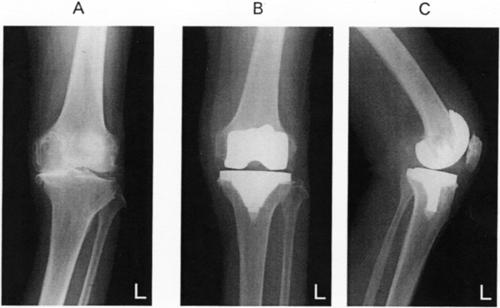

75歳の女性。左膝は、変形と痛みのため、可動域が屈曲20°~90°であった。左人工膝関節手術(セメント使用)を受けた。術前の膝関節エックス線単純正面立位像(別冊No. 2A)、術後の膝関節エックス線単純正面像(別冊No. 2B)および側面像(別冊No. 2C)を別に示す。人工関節にした理由で適切でないのはどれか。

pvzgcnT1Hm0oFlJatc0dz

外反変形が強い。

軟骨の変性が高度である。

人工関節は10~15年の使用に耐えられる。

可動域の改善が望める。

除痛効果が得られる。

75歳の女性。左膝は、変形と痛みのため、可動域が屈曲20°~90°であった。左人工膝関節手術(セメント使用)を受けた。術前の膝関節エックス線単純正面立位像(別冊No. 2A)、術後の膝関節エックス線単純正面像(別冊No. 2B)および側面像(別冊No. 2C)を別に示す。術後2週の運動療法で適切でないのはどれか。

v7IbxaNAf9Q-aD8lx0F5F

足関節の底背屈運動

大腿四頭筋の等尺性運動

体幹筋の強化

膝CPM(持続的他動運動)

平行棒内免荷歩行訓練